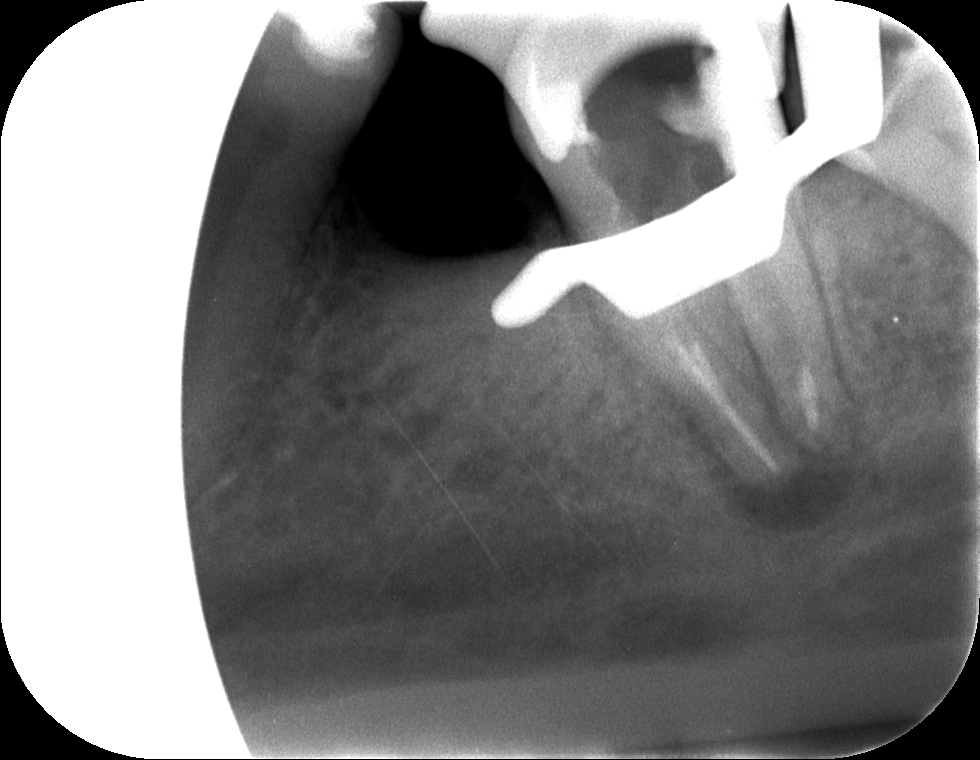

A röntgenfelvételen az elkészült gyökértömés első fázisa látható, amely még nem tölti ki a teljes csatornarendszert, csak a gyökerek végét zárja. A többi csatornaszakasz komplett tömése után üvegszálas csapos megerősítést helyeztünk a fogba.